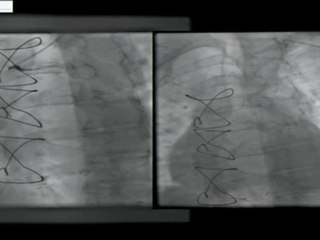

20 bilateral internal mammary artery graft angiogram - radial approach incathlab.com